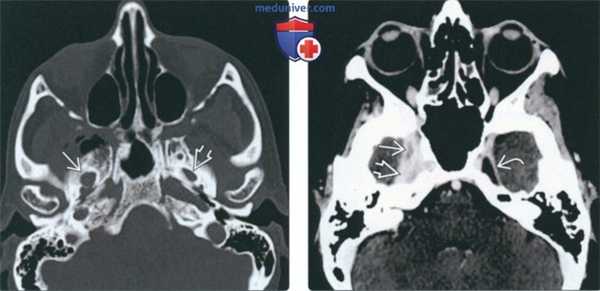

(Слева) На аксиальной МРТ (Т1 ВИ) у пациента, ранее пролеченного по поводу плоскоклеточного рака носоглотки, определяется замещение нормального жирового костного мозга в ветви нижней челюсти справа наряду с патологической мягкой тканью на уровне нижнечелюстного отверстия (ПНО ЧМН V3). Обратите внимание на нормальный гиперинтенсивный сигнал в жировом костном мозге в ветви нижней челюсти слева.

(Справа) На аксиальной МРТ (Т1 ВИ) у этого же пациента определяется ПНО ЧМН V3 с облитерацией жировых плааинок в жевательном пространстве.

(Слева) МРТ Т1ВИ в аксиальной проекции, пациент, которому ранее проводилось лечение по поводу плоскоклеточного рака носоглотки. Костный мозг в правой ветви нижней челюсти замещен опухолевой тканью, на уровне отверстия нижней челюсти также определяется патологическая ткань, появление которой связано с распространением опухоли по нижнечелюстному нерву. Обратите внимание на нормальный костный мозг левой ветви нижней челюсти, который имеет гиперинтенсивный сигнал.

(Справа) МРТ Т1ВИ в аксиальной проекции, этот же пациент. Периневральное распространение опухоли по нижнечелюстному нерву с облитерацией жировой клетчатки жевательного пространства.